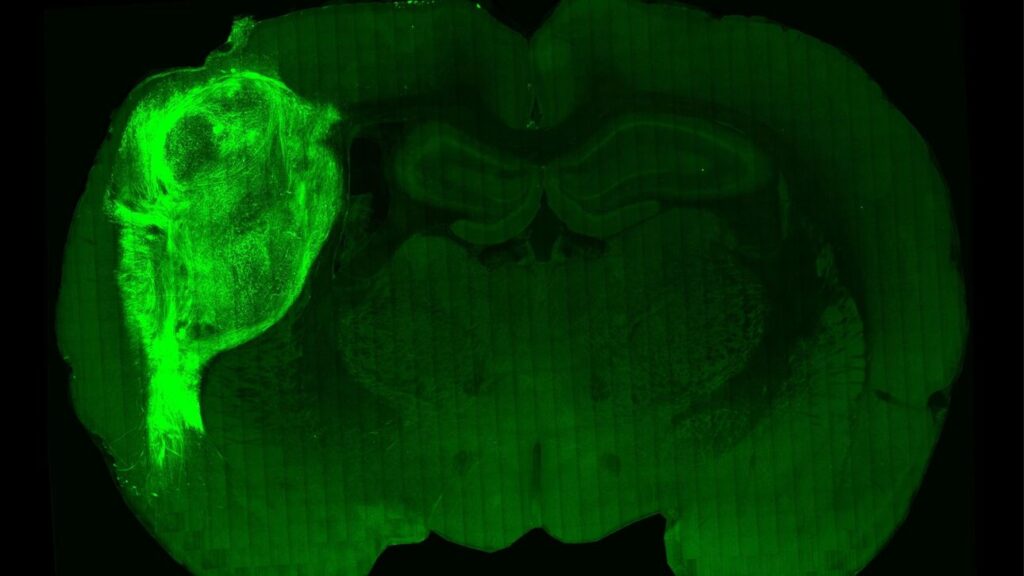

Οι ερευνητές, με επικεφαλής τον καθηγητή ψυχιατρικής και συμπεριφορικών επιστημών Σέρτζιου Πάσκα της Ιατρικής Σχολής του Πανεπιστημίου Στάνφορντ της Καλιφόρνιας, οι οποίοι έκαναν τη σχετική δημοσίευση στο περιοδικό «Nature», εμφύτευσαν οργανοειδή ανθρώπινου εγκεφάλου (κυτταρικές καλλιέργειες εργαστηρίου που δημιουργούν μίνι-εγκεφάλους) στον σωματοαισθητικό φλοιό του εγκεφάλου 100 νεογέννητων αρουραίων ηλικίας δύο έως τριών ημερών.

Οι εγκέφαλοι των ζώων ενσωμάτωσαν ομαλά το μόσχευμα, το υποστήριξαν με νέα αιμοφόρα αγγεία και το προστάτευσαν με ανοσοκύτταρα. Έτσι οι ανθρώπινοι νευρώνες πολλαπλασιάστηκαν και τελικά κάλυψαν περίπου το ένα τρίτο του ενός ημισφαιρίου του εγκεφάλου των ζώων. Όπως είπε ο Πάσκα, «ήταν σαν να προσθέτεις άλλο ένα τρανζίστορ σε ένα ηλεκτρονικό κύκλωμα». Τελικά οι ανθρώπινοι νευρώνες σχημάτισαν συνδέσεις (συνάψεις) με τα εγκεφαλικά κυκλώματα των αρουραίων και κατέληξαν να επηρεάζουν τη συμπεριφορά τους, ενώ δεν φάνηκαν κάποιες παρενέργειες στα ζώα.